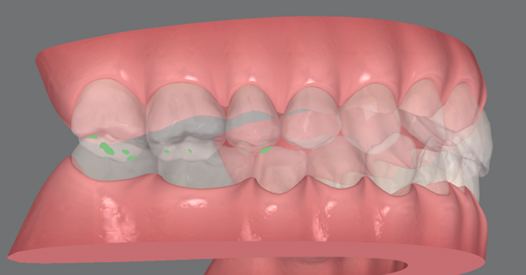

1.歯全体で噛めず、奥歯だけが強く当たる状態になっていた

顎関節を正しい位置にしたときに、歯のどこが噛んでいるのか、3Dデータで分析しました。上の写真で緑色の箇所が、歯同士が強く接触している部分です。両側の一番奥の歯が、強く当たっていることがわかります。一方、前歯には緑色がほとんどついていないこともわかります。

「正常な噛み合わせとは」で説明したように、本来は、歯が全体的に当たっているのが好ましい状態です。

しかし今の状態だと、奥歯が先に当たってしまうことで、歯全体でうまく噛めないことが予想されます。このような場合、習慣的に顎を前にずらすようにしないと、うまく噛めません。このズレを補正して、食いしばり・歯ぎしりの力が強くなったり、頻度が増えたりするというデータがあります。